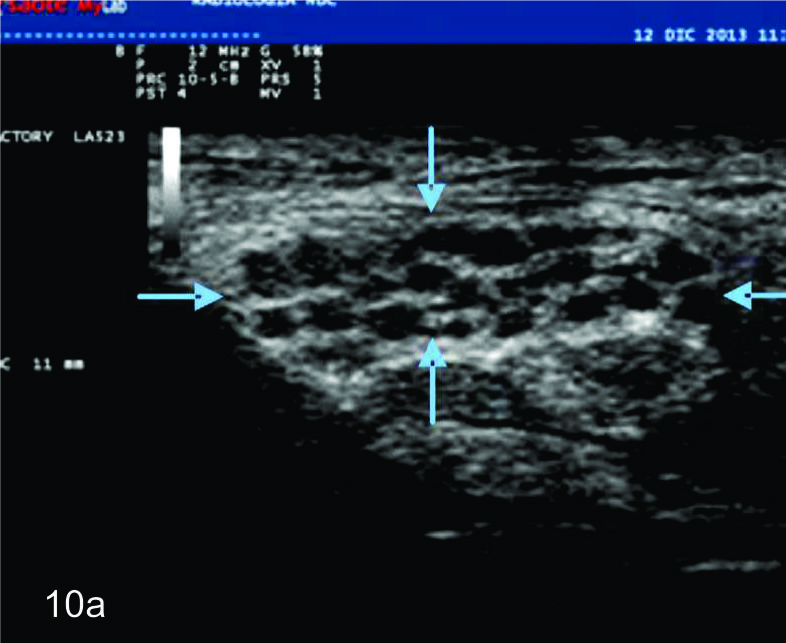

Figura 10

Hamartoma fibrolipomatoso del nervio mediano

A y B, cortes transversales en antebrazo y puño, las flechas azules señalan al nervio mediano aumentado de tamaño con fascículos engrosados. C- Corte longitudinal con hallazgos similares en plano longitudinal del nervio (flechas azules).

Dada las características ultrasonográficas normales de los nervios, algunas variantes anatómicas pueden ser reconocidas por este método. Entre ellas la bifurcación proximal del mediano en el puño es una de las más frecuentes. De manera similar algunas anomalías heredables y del desarrollo del sistema nervioso periférico, como el agrandamiento fusiforme del nervio mediano por tejido fibroadiposo (denominado hamartoma fibrolipomatoso (Fig.10), la hipertrofia de los nervios en el síndrome de Charcot-Marie-Tooth y el aumento de los nervios en la neuropatía hereditaria secundaria a parálisis por compresiones pueden ser reconocidas por ultrasonido. En estas enfermedades, los hallazgos ultrasonográficos pueden contribuir a la comprensión de la fisiopatología demostrando de forma no invasiva algunos hallazgos morfológicos de interés (1).